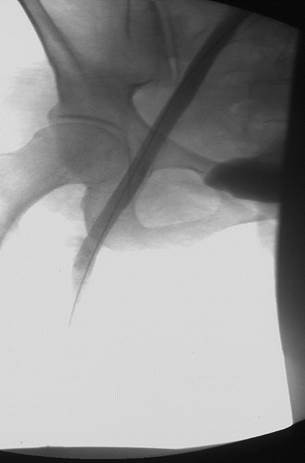

Acceso poplíteo; vista de posición decúbito prono de un trombo oclusivo agudo en la vena poplítea izquierda y en la vena femoral.

Acceso poplíteo; vista de posición decúbito prono de un trombo oclusivo agudo en la vena femoral izquierda y en las venas ilíacas.